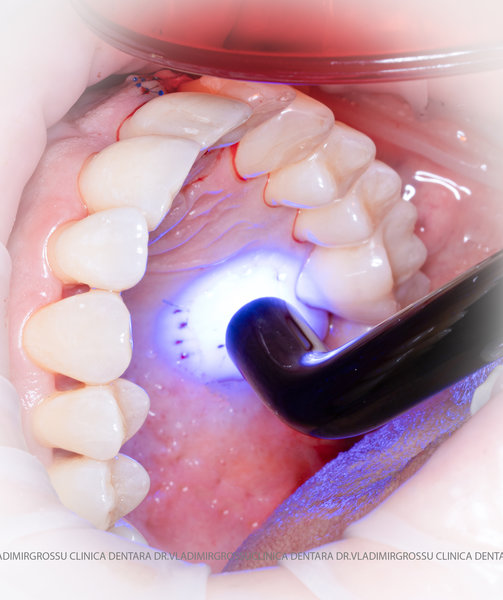

Un element esențial în procedura de aditie osoasă este utilizarea membranelor biologice, care izolează materialul osos de țesuturile moi (gingie) pe durata procesului de vindecare. Cele mai recomandate sunt membranele resorbabile din colagen sau pericard.

Aditia gingivală este o procedură chirurgicală ce corectează diverse probleme estetice și funcționale, cum ar fi recesiunea gingivală. În implantologia modernă, aditia de țesut moale este utilizată aproape în fiecare intervenție de inserție a implantului dentar pentru a asigura un aspect estetic natural și o bună integrare a implantului în cavitatea bucală.

Adiția osoasă are un rol crucial pentru poziționarea corectă și stabilă a implanturilor dentare. Clinica stomatologică Dr. Grossu din Chișinău promovează o abordare chirurgicală estetică și predictibilă, adaptată fiecărui caz în parte.